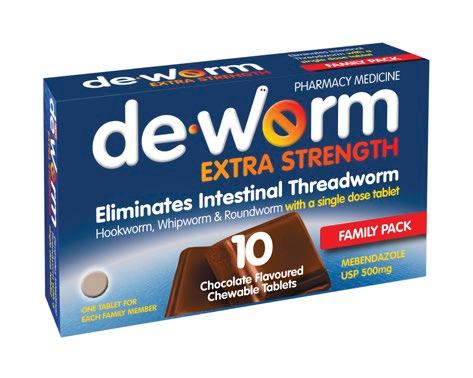

Eliminates intestinal threadworm with one single-dose tablet Chocolate flavoured chewable tablets Available in packs of 2, 4, 6 and new 10 Tablet Family Pack Soothes the throat Contains Manuka honey Supports immune heath Blended with Wellmune® for immune health support and natural New Zealand Manuka honey to coat the throat. Bursting with delicious and soothing flavours. Effective worm treatment Soothe dry, tickly throats De-Worm Extra Strength 500mg 2 Tabs $699 4 Tabs $999 6 Tabs $1199 $1399 Multichem NZ Ltd, Auckland $699 20 Tabs Radiant Health Ltd, Auckland Pharmac y only me dicine O ne t ablet once for any memb er of the family 2 year s and over Radiant H ealth Ltd , Auckland SEE F ULL RANGE I N S T O R E GREAT CHOCOLATE FLAVOUR KI LL S WO RM S ONE TABLET ONCE Vermox Choc Chews 4 pack $1399 De-Worm Extra Strength 500mg Family Pack 10 Tabs Offers and advertised products may not be available at all participating pharmacies. Offers are valid from Monday 6 March to Friday 24 March 2023 or while stocks last. Prices printed in this brochure are Recommended Retail Prices (RRP). Always read the label. Use only as directed. If symptoms persist see your doctor or health professional. Vitamins are supplementary to a balanced diet. Full product information is available from your pharmacy TAPS PP9728. BACK TO SCHOOL ESSENTIALS